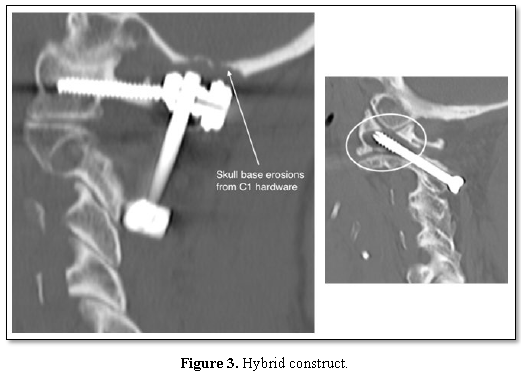

Only one study has previously reported the use of the hybrid fixation technique which may be required for anomalies such as a high-riding vertebral artery [5]. The 8 patients in this series who had hybrid fixations achieved identical results to those with TAS or Harms constructs (Figure 3). Our patients report satisfaction with their surgery of greater than 90%, with dramatic improvement in VAS and NDI scores postoperatively. This indicates that posterior atlantoaxial fixation is a highly successful surgical technique for the treatment of symptomatic AAOA.